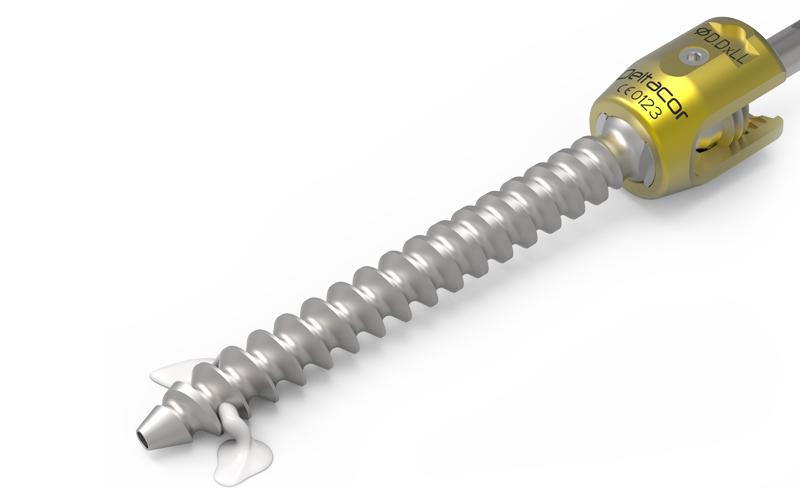

zurückKINERAAugmentation

KINERA erlaubt bei osteoporotischem Knochen durch seine Fenestierungen im Gewindekörper eine feste Verankerung der Pedikelschraube mittels Zementinjektionen.Der Zement wird direkt über Applikationshülsen durch die Kanülierung der Schraube eingebracht. Am distalen Ende des Gewindes tritt der hoch visköse Zement durch die Fenestierung langsam in den trabekulären Strukturen des Wirbelkörpers aus.